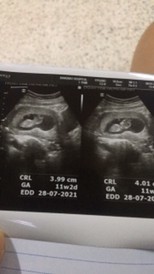

11w2dค่ะตอนนี้18wแล้ว